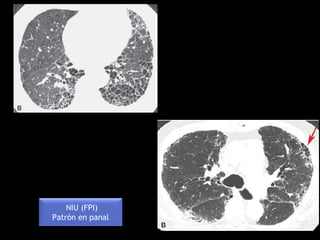

NIU (FPI)

Patrón en panal